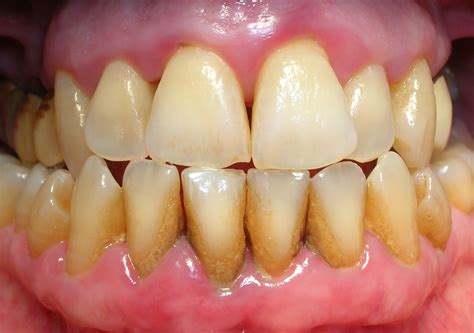

El sarro es por tanto resultado del endurecimiento de esa placa bacteriana no retirada. Forma un recubrimiento blanquecino o amarillento en la base de los dientes, en especial en los dientes inferiores anteriores por el lado de la lengua y en los molares superiores por el lado de la mejilla. La placa puede eliminarse mediante el cepillado diario, sin embargo, el sarro no puede eliminarse mediante cepillado y solo pueden eliminarlo adecuadamente un dentista o un higienista dental.

El sarro tiene la apariencia de una costra gruesa que cubre los dientes, sobre todo la parte trasera de las piezas delanteras inferiores, que es una zona más difícil de limpiar. También puede formarse entre las piezas dentales y el borde de las encías.

Inicialmente su color es blanquecino, pero se mancha con facilidad y puede adquirir un tono amarillento o amarronado. Asimismo, puede presentarse acompañado de hinchazón y enrojecimiento de las encías, cuadro conocido como gingivitis.

- Gingivitis. La placa y el sarro irritan e inflaman las encías, que se hinchan y sangran. Se pueden formar “bolsillos” en los que pueden proliferar bacterias.

A medida que el sarro se acumula a lo largo y debajo de la línea de las encías, irrita los delicados tejidos de las encías, lo que provoca inflamación y gingivitis. Si no se aborda de inmediato, la gingivitis puede progresar a periodontitis, una forma más grave de enfermedad de las encías.